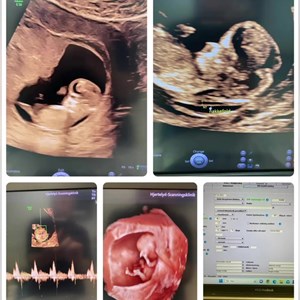

hjertelyd_scanningsklinik Se lige ham den lille charmetrold her 😍 Tilbagelænet stil med ...

Veloverstået lørdag formiddag TAK for alle jer ‼️🫶🏼 11 babyer med følge af forældre, s...